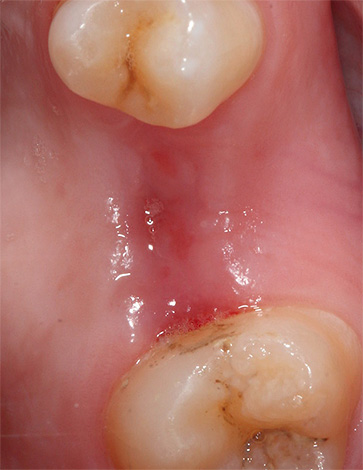

A convergência completa das bordas da ferida com uma extração dentária realizada qualitativamente ocorre normalmente em 2-2,5 semanas. Simultaneamente à epitelização, ocorrem a formação de feixes ósseos e o desenvolvimento de ossos jovens.

Com um dente traumaticamente rasgado (quando os tecidos circundantes são esmagados e rasgados), a cicatrização das gengivas se estende por um longo tempo, porque após a remoção ocorre uma laceração, cujas bordas estão frequentemente muito afastadas e as seções dos alvéolos (osso) e da lacuna do septo inter-radicular, não cobertas pela margem gengival. Quando a inflamação do tecido ocorre dentro e ao redor do poço, as bordas da ferida não se juntam por muito tempo e a epitelização não termina após 2 semanas, mas pode levar de 30 a 50 dias.

Somente após 4-5 meses, a formação de tecido ósseo jovem é concluída e a versão final da "cobertura" gengival é formada sobre o orifício.